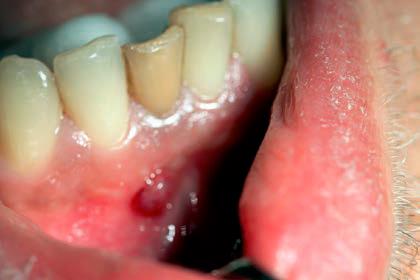

Ryc. 9. Przetoka czynna w przedsionku jamy ustnej, zlokalizowana w okolicy zębów 41-42.

Źródło: Olczak K, Pawlicka H. Zastosowanie rentgenodiagnostyki w endodoncji. Mag Stomatol. 2019; 9: 30.

Jeszcze w stosunkowo niedalekiej przeszłości pokutowało wśród pacjentów (i niestety również wśród niektórych lekarzy dentystów) przekonanie, że zęby będące przyczyną stanów ropnych należy usunąć. Tymczasem można te zmiany skutecznie leczyć, a aktywny wysięk opanować czasami zaledwie w trakcie kilku dni (ryc. 9‑11). Dopiero w przypadku niepowodzenia terapii zachowawczej należy rozpatrzyć zastosowanie zabiegu endodontyczno‑chirurgicznego lub w skrajnych przypadkach usunięcie zęba. W wielu przypadkach można też przeprowadzić leczenie jednowizytowe, nawet jeśli występują przewlekłe zmiany zapalne w tkankach okołowierzchołkowych (20‑23). Gdy leczenie na jednej wizycie jest niemożliwe, najczęściej zaleca się stosowanie opatrunku na bazie wodorotlenku wapnia. Działanie lecznicze preparatów wodorotlenkowo‑wapniowych jest związane z ich wysokim pH oraz z uwalnianiem jonów wapniowych i hydroksylowych (21, 23). Jony hydroksylowe powodują obniżenie ciśnienia tlenu i wzrost pH w tkankach zmienionych zapalnie. Jony wapniowe stymulują fosfatazę zasadową do wytwarzania zębiny i naprawy kości oraz wpływają na miejscowe reakcje immunologiczne. Niskie ciśnienie i alkaliczne środowisko sprzyjają procesom mineralizacji naprawy. Bakteriobójcze działanie wodorotlenku wapnia polega na niszczeniu cytoplazmatycznej błony komórek bakteryjnych oraz destrukcji struktur białkowych i DNA (23).

Ryc. 11. Zastosowano antyseptyczne leczenie kanałowe zęba 31. Po tygodniu przetoka uległa wygojeniu.